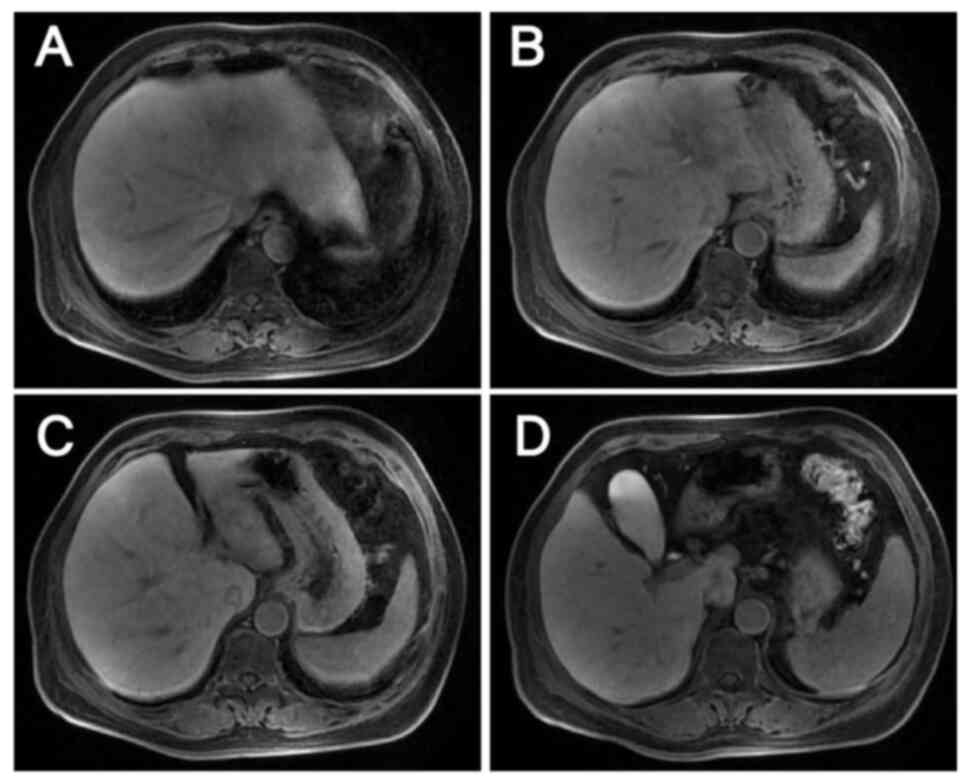

Initial assessment of the liver

lesions by magnetic resonance imaging on October 20, 2023. (A-C)

Metastases in the S2, S3 and S4 segments and (D) two enlarged lymph

nodes, one anterior and one posterior to the portal vein are shown.

Lesions are indicated by arrows.

Figure 3.

Initial assessment of the liver lesions by magnetic resonance imaging on October 20, 2023. (A-C) Metastases in the S2, S3 and S4 segments and (D) two enlarged lymph nodes, one anterior and one posterior to the portal vein are shown. Lesions are indicated by arrows.

EGFR inhibitor therapy was not considered due to the NGS result and the evidence suggesting that patients with HER2-positive CRC are highly resistant to EGFR inhibitors (11,12). Furthermore, targeted bevacizumab therapy was not started because hemorrhage is one of the most serious adverse effects of bevacizumab and the patient had persistent hematochezia. In light of the recent developments in CRC research and the financial circumstances of the patient, single-agent anti-HER2 therapy combined with a modified FOLFOX6 regimen was selected as the subsequent treatment, in which the doses of chemotherapeutic agents were adjusted and administered on a 3-week cycle. The patient received six cycles of trastuzumab 450 mg + FOLFOX, with the latter comprising oxaliplatin 150 mg + leucovorin calcium 600 mg + fluorouracil 0.625 g by injection + fluorouracil 4 g by continuous intravenous drip. These agents were administered on 41 days post admission, 62 days post admission, 83 days post admission, 108 days post admission, 134 days post admission, and 157 days post admission. During treatment, the tumor marker levels gradually decreased (Fig. 4), and computed tomography (CT) and magnetic resonance scans of the liver indicated a marked reduction in the size of the tumor lesions (Fig. 6, Fig. 7, Fig. 8, Fig. 9). This was evaluated as a partial response.